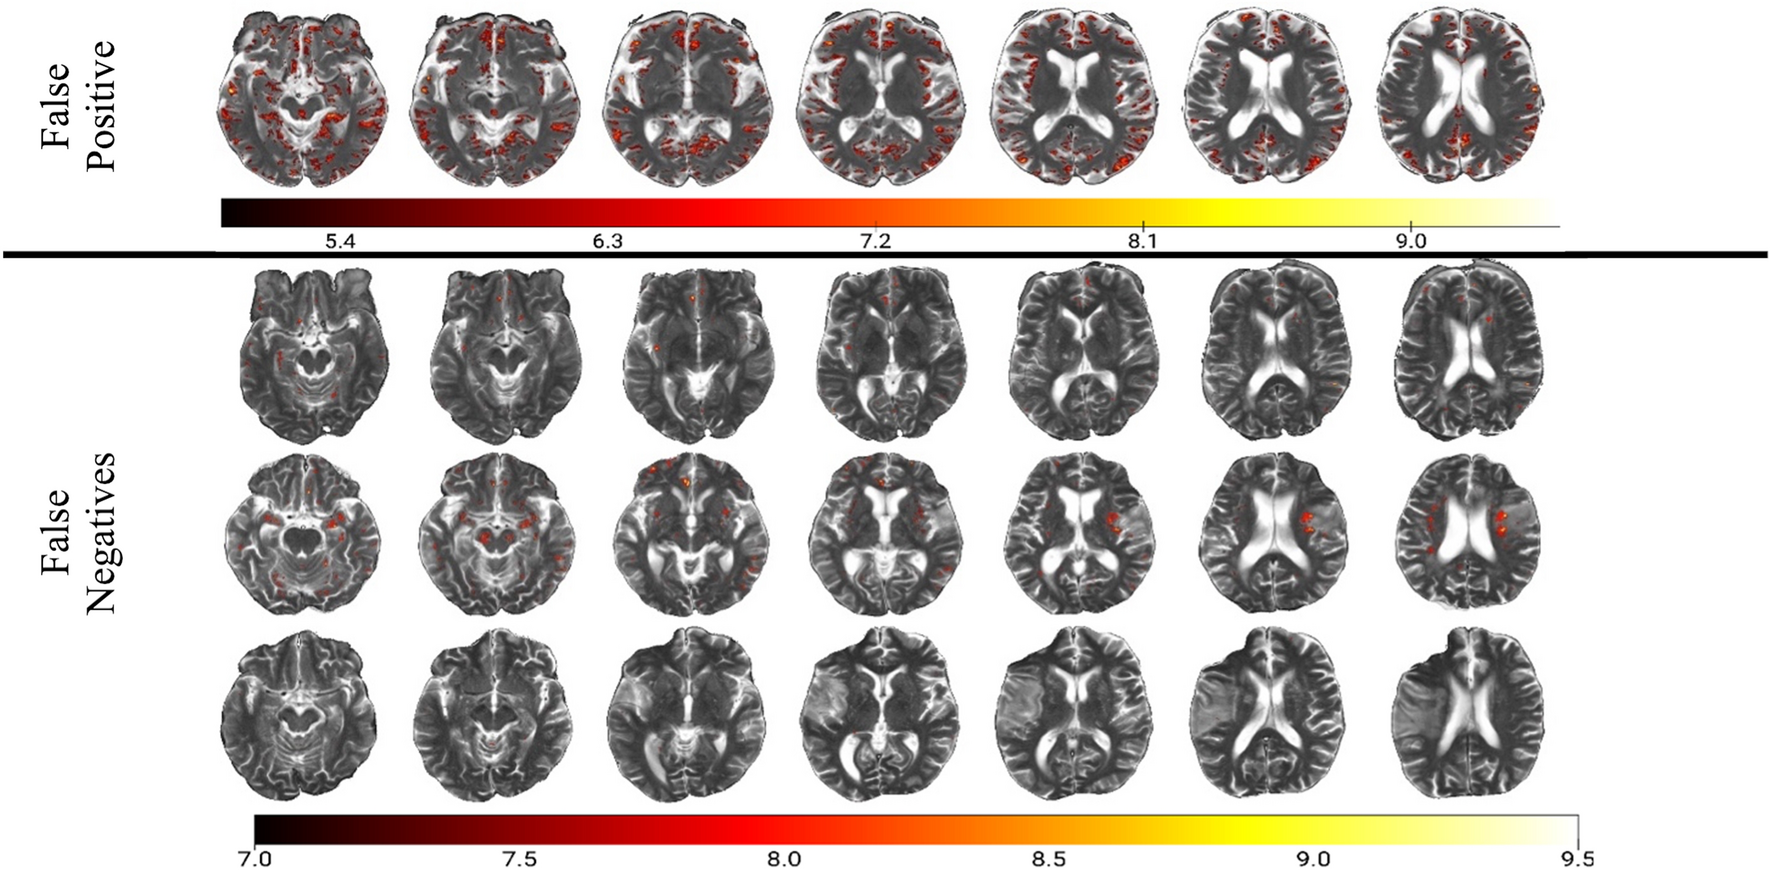

Figure 3

Analysis of misclassified patients. In the false positive case, the network seems to have picked up on remote infarcts that often resemble EPVS. In the false negative cases, there were less activations in the high range (> 7), i.e. activations were more homogenous.